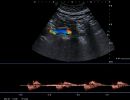

- Αιμοδυναμικές Διαταραχές: Mε τη χρήση του Έγχρωμου και του Παλμικού Doppler μπορούν να μελετηθούν οι ταχύτητες της αιματικής ροής και να ανιχνευθούν πιθανές αιμοδυναμικές διαταραχές.

- Αγγειακή Στένωση: Η αξιολόγηση της αιματικής ροής μπορεί να οδηγήσει στη διάγνωση στένωσης των αγγείων και να υπολογιστεί ο βαθμός της στένωσης.